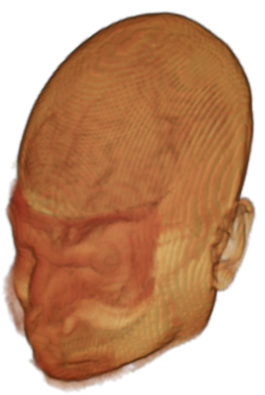

The digitalization of heath records has increased the risk of –and impact of– large scale data leaks. Although data compliance standards have been enacted to protect health records (HIPAA and GDPR), privacy of medical data is a growing concern. Three-dimensional scans such as magnetic resonance images (MRI) and computed tomography (CT), for example, contain an intrinsic privacy risk [Lotan et al.(2020)Lotan, Tschider, Sodickson, Caplan, Bruno, Zhang, and Lui]. Detailed renderings of the head can be crafted from 3D scans using techniques such as volumetric raycasting, as in Figure 1. This vulnerability can expose the patient’s identity if the renderings are matched to a face database [Mazura et al.(2012)Mazura, Juluru, Chen, Morgan, John, and Siegel, Lotan et al.(2020)Lotan, Tschider, Sodickson, Caplan, Bruno, Zhang, and Lui].

To prevent these types of attack, medical scans are currently de-identified using crude removal-based techniques [Bischoff-Grethe et al.(2007)Bischoff-Grethe, Ozyurt, Busa, Quinn, Fennema-Notestine, Clark, Morris, Bondi, Jernigan, Dale, Brown, and Fischl, Schimke et al.(2011)Schimke, Kuehler, and Hale, Milchenko and Marcus(2013)] which seek to remove privacy-sensitive parts of the head (examples in Figure 3). However, as we demonstrate, these existing techniques fail to reliably hide the patient’s identity – or they are so aggressive that they impair further medical analyses. A better solution is needed.

![]() |

Therefore, in this work, we define a new class of de-identification techniques that remodels the privacy-sensitive regions without altering the content of medically relevant data (see Figure 1). Under such a remodeling approach, the face, eyes, oral and nasal cavities, etc. should exhibit realistic appearance and structure of appropriate size, but should otherwise be independent of the original data. To solve this task, we propose a novel model called Convex Privacy GAN, or CP-GAN, that conditions on a convex hull of the skull extracted from the scan to be de-identified. The generator learns to synthesize volumes that preserve medically-sensitive regions such as the brain, while non-invertibly remodeling privacy-sensitive characteristics from the original scan.